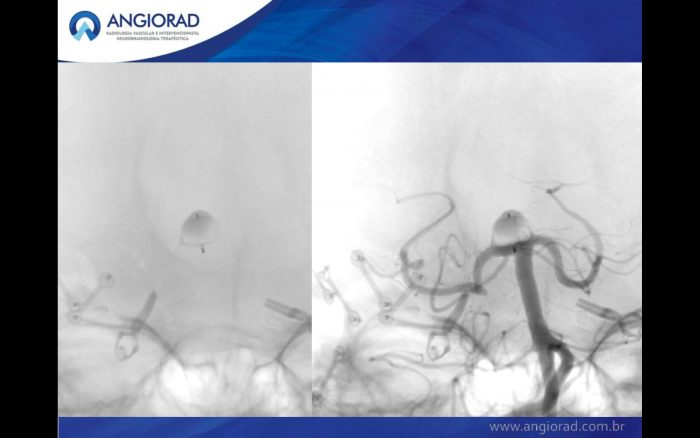

Paciente com diagnóstico de aneurisma incidental de topo de artéria basilar (fig1).

A interrupção do fluxo do aneurisma com o dispositivo WEB (Woven EndoBridge – Microvention Terumo) é uma abordagem endovascular inovadora para o tratamento de aneurismas de bifurcação de colo largo. Estudos iniciais mostraram uma baixa taxa de complicações com boa eficácia.